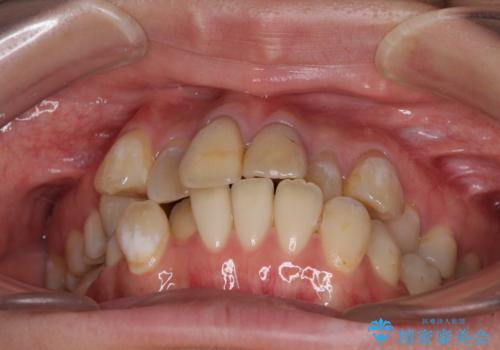

- 前歯の八重歯やデコボコを気にして来院された患者様です。

口元の突出感はありませんが、前歯の重なりが著しいため、目立ちにくい表側のワイヤー装置にて、上下左右の第一小臼歯4本を抜歯して矯正治療を行うこととしました。

上顎前歯4本は、以前むし歯により神経をすべて取り除かれており、その影響で既に変色を起こしている状態でした。